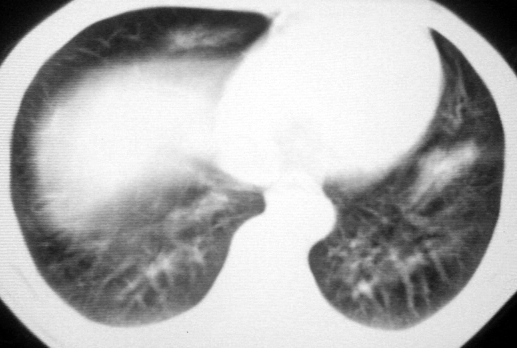

男,36岁,一月前醉酒淋雨后发热咳嗽,气短进行性加重.

抗生素治疗无效,痰检(一).

影像诊断:结核? 还有其他考虑吗?

双肺内中部见略不对称性蝶翼状高密度区,边界不清,部分呈磨玻璃样密度,并可见含气支气管征。肺门、纵隔内未见肿大淋巴结影。无胸腔积液。

考虑:1、肺炎,建议进一步查冷凝集试验除外支原体肺炎;

2、不除外霉菌感染。

双肺斑片状密度均匀病灶,边界模糊可见充气支气管征,上野多于下野,不支持结核,1肺内感染,2查肾功,中心型肺水肿待除外.

双肺中上野对称分布蝶翼样不均匀密度增高影,有支气管充气征,纵隔未见肿大淋巴结,发病突然,抗炎治疗无效,还是要考虑结核。

还是考虑肺水肿!蝶翼征.肺门增大,肺血管影增粗,!!病变累及中内带为主!要排外支原体感染.

支持: 双肺内中部见略不对称性蝶翼状高密度区,边界不清,部分呈磨玻璃样密度,并可见含气支气管征。肺门、纵隔内未见肿大淋巴结影。无胸腔积液。